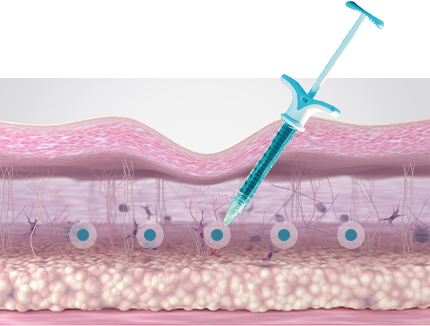

คอลลาเจน เป็นเส้นใยโปรตีนที่เป็นส่วนประกอบของผิวหนัง ช่วยยึดเกาะ

เพิ่มความยืดหยุ่นและความชุ่มชื้นแก่ผิว โดยปกติร่างกายจะสามารถผลิตคอลลาเจนได้เอง

แต่เมื่ออายุมากขึ้น ร่างกายจะสามารถสร้างคอลลาเจนได้น้อยลง

ซึ่งทำให้ผิวหนังหย่อนคล้อยและเกิดริ้วรอยตามวัยได้

ลดความหย่อนคล้อย